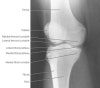

2. A/P Knee View

Demonstrates: femorotibial articulation

Helpful for: Knee Arthritis, Tibial Plateau Fracture, Distal Femur Fracture

Position: supine with cassette under knee and femoral condyles parell to cassette.

Beam directed to point 1-2cm distal to the patella.